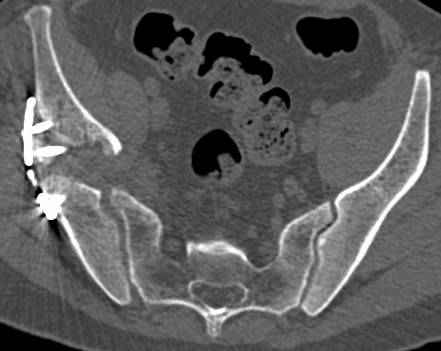

Интересно было бы посмотреть рентгенограммы до операции. У меня впечатление, что я не все вижу, что тут есть... Уважаемые Господа "тазисты" и "тазологи", к какому типу переломов вертлужной впадины по Летурнелю вы бы отнесли это случай?

Из переломов проходящих через крыло и/или заднюю стенку ни простой перелом "передней колонны" (явно имеется пером задней стенки, и не видно перелома седалищной или лонной), ни простой "поперечный", ни ассоциированный "Т-образный" (т.к есть перелом крыла и не видно перелома седалишной), ни ассоциированный "задняя колонна+задняя стенка", на ассоциированный "поперечный+задняя стенка", ни ассоциированный "передняя колонна+задняя гемисфера" (не видно перелома седалищной), ни ассоциированный "обе колонны" (не видно перелома лонной седалищной) не подходят под эту классификацию....

к таковым себя не причисляю, но...обычное дело для нашей страны - выкладывать 3D и не показывать стандартные проекции Judet. Дигност представляет те ракурсы, которые по-его мнению наиболее информативны, более того комп сам достраивает какие-то мелкие повреждения по 3D по своему усмотрению. По данной реконструкции можно предполагать высокий двухколонный перелом с оскольчатыми передней и задней колоннами, оскольчатую высокую переднюю колонну с задним полупоперечником или одно из перечисленных с вовлечение КПС. У меня впечатление за второй вариант, но нужно обследовать нормально - проекции, сканы.

высылаю дополнительно сканы.